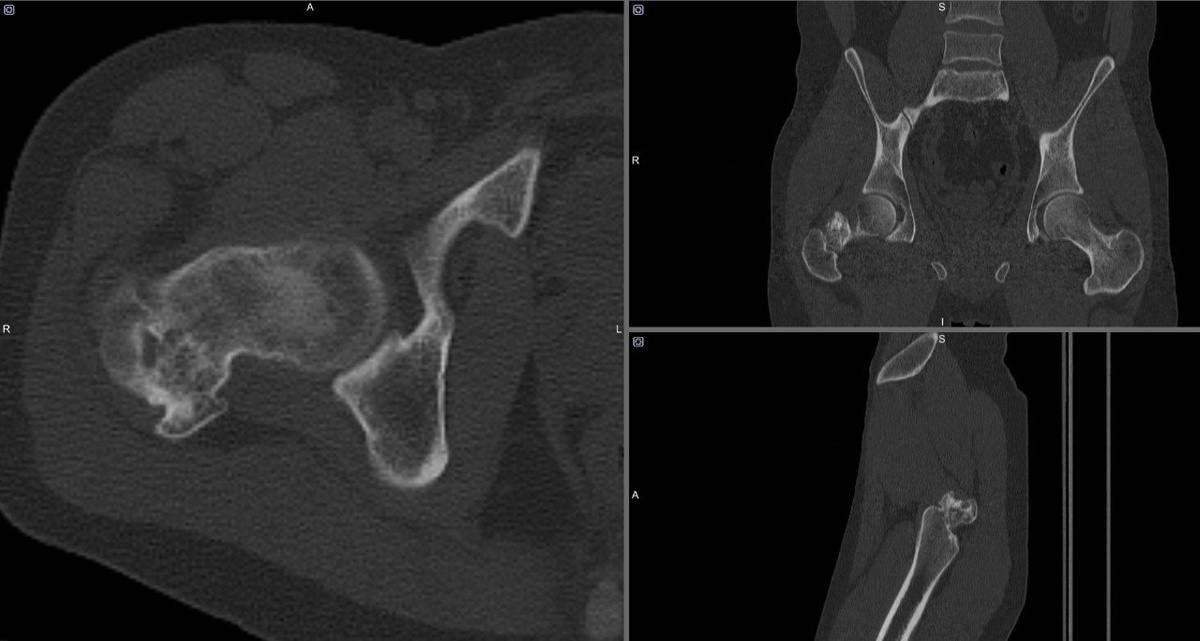

! Пациенту было выполнено КТ, в результате которого в шейке бедренной кости было обнаружено образование. Молодой человек далее был направлен на остеосцинтиграфию, на которой было выявлено, что данное образование также накапливает радиофармпрепарат. Ваши варианты, что за образование у пациента и каков механизм накопления РФП?